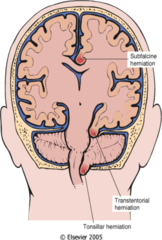

Hydrocephalus

Communicating (decreased CSF absorption by arachnoid granulations) - post-meningitis scarring - Arnold-Chiaria malformation - choroid-plexus tumor overproducing CSF Non-communicating (obstructive) - foramen of monro (lateral --> 3rd) - cerebral aqueduct (3rd --> 4th) Normal pressure hydrocephalus - increased CSF and dilated ventricles BUT normal pressure - wet (incontinence), wacky (dementia), wobbly (ataxia) Hydrocephalus ex vacuo - atrophy of brain tissue leads to compensatory increase in CSF (alzheimer's, HIV, Pick)